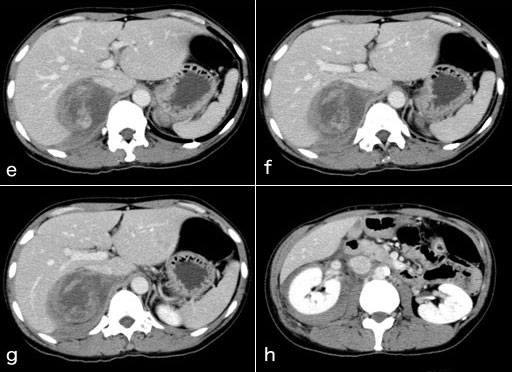

図1 発症当日のCT

• 造影CTe~h